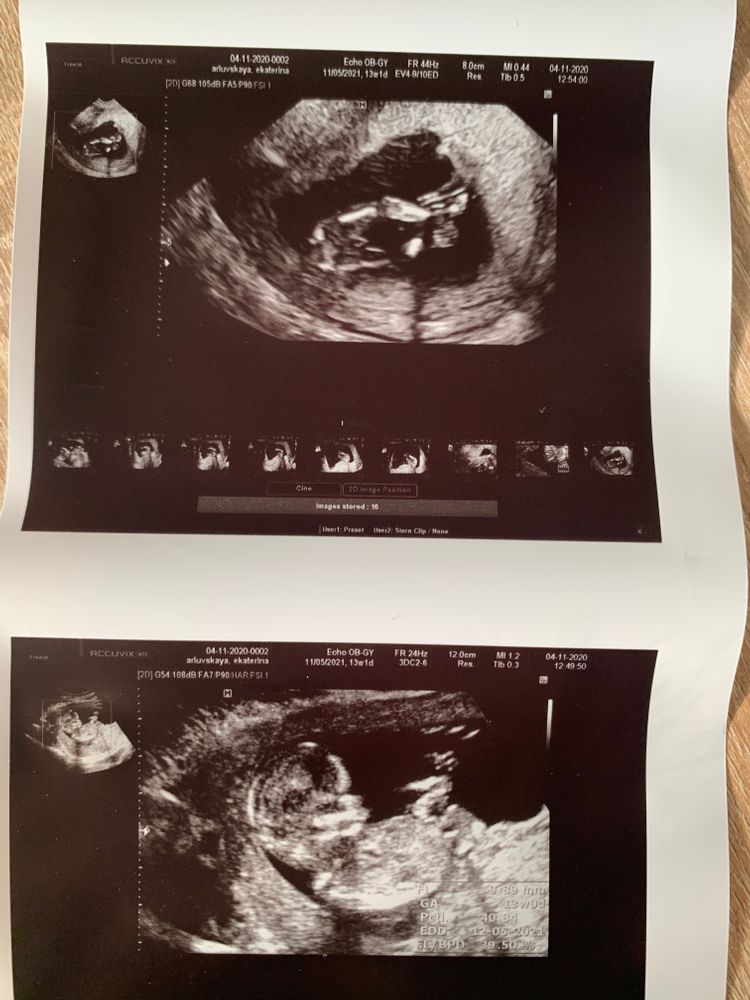

Скрининг 13 недель

Еще рано, поверьте, то что торчит не значит еще что это мальчик. Бугорок у них есть у всех на этом сроке, нужно смотреть на угол этого бугорка, а у вас сбоку не видно. У меня тоже явно чтото торчало на первом скрининге, особенно как врач 3д включил, я сама это видела, и он из-за этогт предположил мальчика. НИПТ показал девочку и ее подтверил тот самый врач, но уже на втором скрининге, никакого бугорка не осталось, а такой себе конкретный девичий цветочек.

Если в 16-20 недель с этого же ракурса все останется так же,то точно мальчишка))

Мальчик точно

Похоже парень 😍😇

Все кто писали что это мальчик, вы были правы, это действительно мальчик 🥰 сегодня пришел анализ крови

Конечно мальчик. Там даже сбоку видно бугорок

Я конечно не специалист. Но по мне, это 💯 мальчик.

Да, скорее всего мальсишка